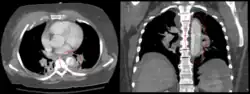

Aortic dissection

CT with contrast demonstrating aneurysmal dilation and a dissection of the ascending aorta (type A Stanford)

Chest CT with descending (type B Stanford) aortic dissection (red circle)

Type A dissection with pericardial effusion as a result.